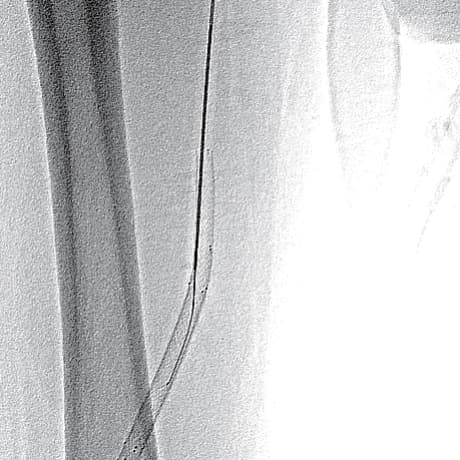

- ステント近位端のみではなく、遠位端やBMSとDESとの重複留置部の硬化が強く難渋したが、なんとか閉塞病変を通過(図3)